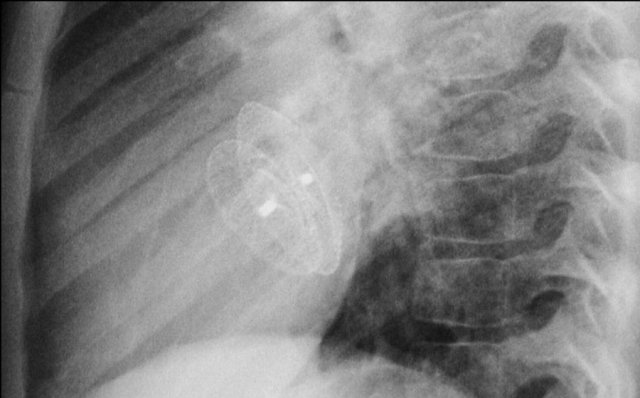

Epicardial pacing leads

Epicardial leads are frequently placed during cardiac surgery in order to allow cardiac pacing post-surgery.

Some centers place them in all cardiac surgery patients, while others only in those who have rhythm disturbances intra-operatively.

After a few days they can be removed by simple traction.

Sometimes they are left in place.

First study the images.

Then continue reading.

The findings are:

• Two epicardial leads connected to pacemaker

• ICD

• two leads to right ventricular apex

• one lead contains two shock coils

• tricuspid valve (arrows)

• mitral valve